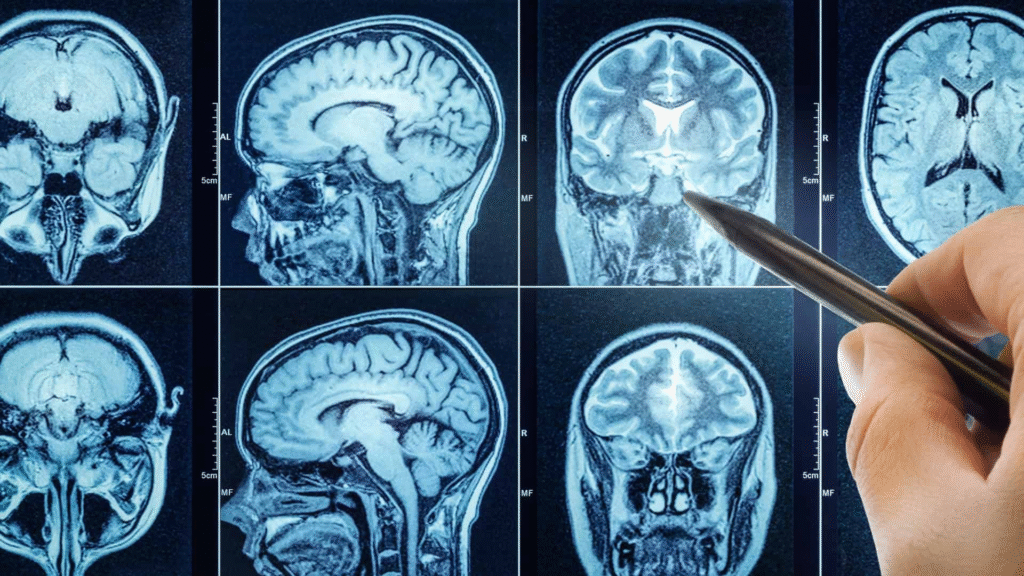

Pesquisadores liderados pela Universidade da Pensilvânia descobriram que a hidralazina — um dos remédios mais antigos usados no tratamento de pressão alta — pode ter um segundo efeito significativo: interromper o crescimento de tumores cerebrais agressivos. A equipe publicou os resultados na Science Advances, revelando pela primeira vez o mecanismo molecular de ação do medicamento e sugerindo novas possibilidades terapêuticas.

O estudo também revelou uma ligação biológica inesperada entre distúrbios hipertensivos e câncer cerebral. Pesquisas anteriores já indicavam que tumores como o glioblastoma dependem da enzima ADO para sobreviver em regiões com pouco oxigênio. Entretanto, faltava um inibidor confiável para explorar essa via.

Com apoio de bioquímicos e neurocientistas de universidades dos EUA, os cientistas testaram a hidralazina diretamente em células de glioblastoma. As descobertas mostram que:

- o mesmo caminho bioquímico que regula a contração dos vasos ajuda as células tumorais a sobreviver em baixa oxigenação;

- ao bloquear a ADO, o remédio induz um estado de “senescência”, no qual as células param de se multiplicar sem gerar inflamação adicional;

- o medicamento não age como quimioterapia tradicional, mas sim interrompe o ciclo de crescimento tumoral.

Esse comportamento sugere que o remédio para pressão alta pode atuar como um modulador biológico, abrindo uma janela para novos tratamentos contra tumores cerebrais altamente agressivos.

Com a identificação da ADO como alvo principal, os pesquisadores planejam desenvolver novas versões do fármaco capazes de atravessar com mais eficiência a barreira hematoencefálica e agir de forma mais seletiva no tecido tumoral.